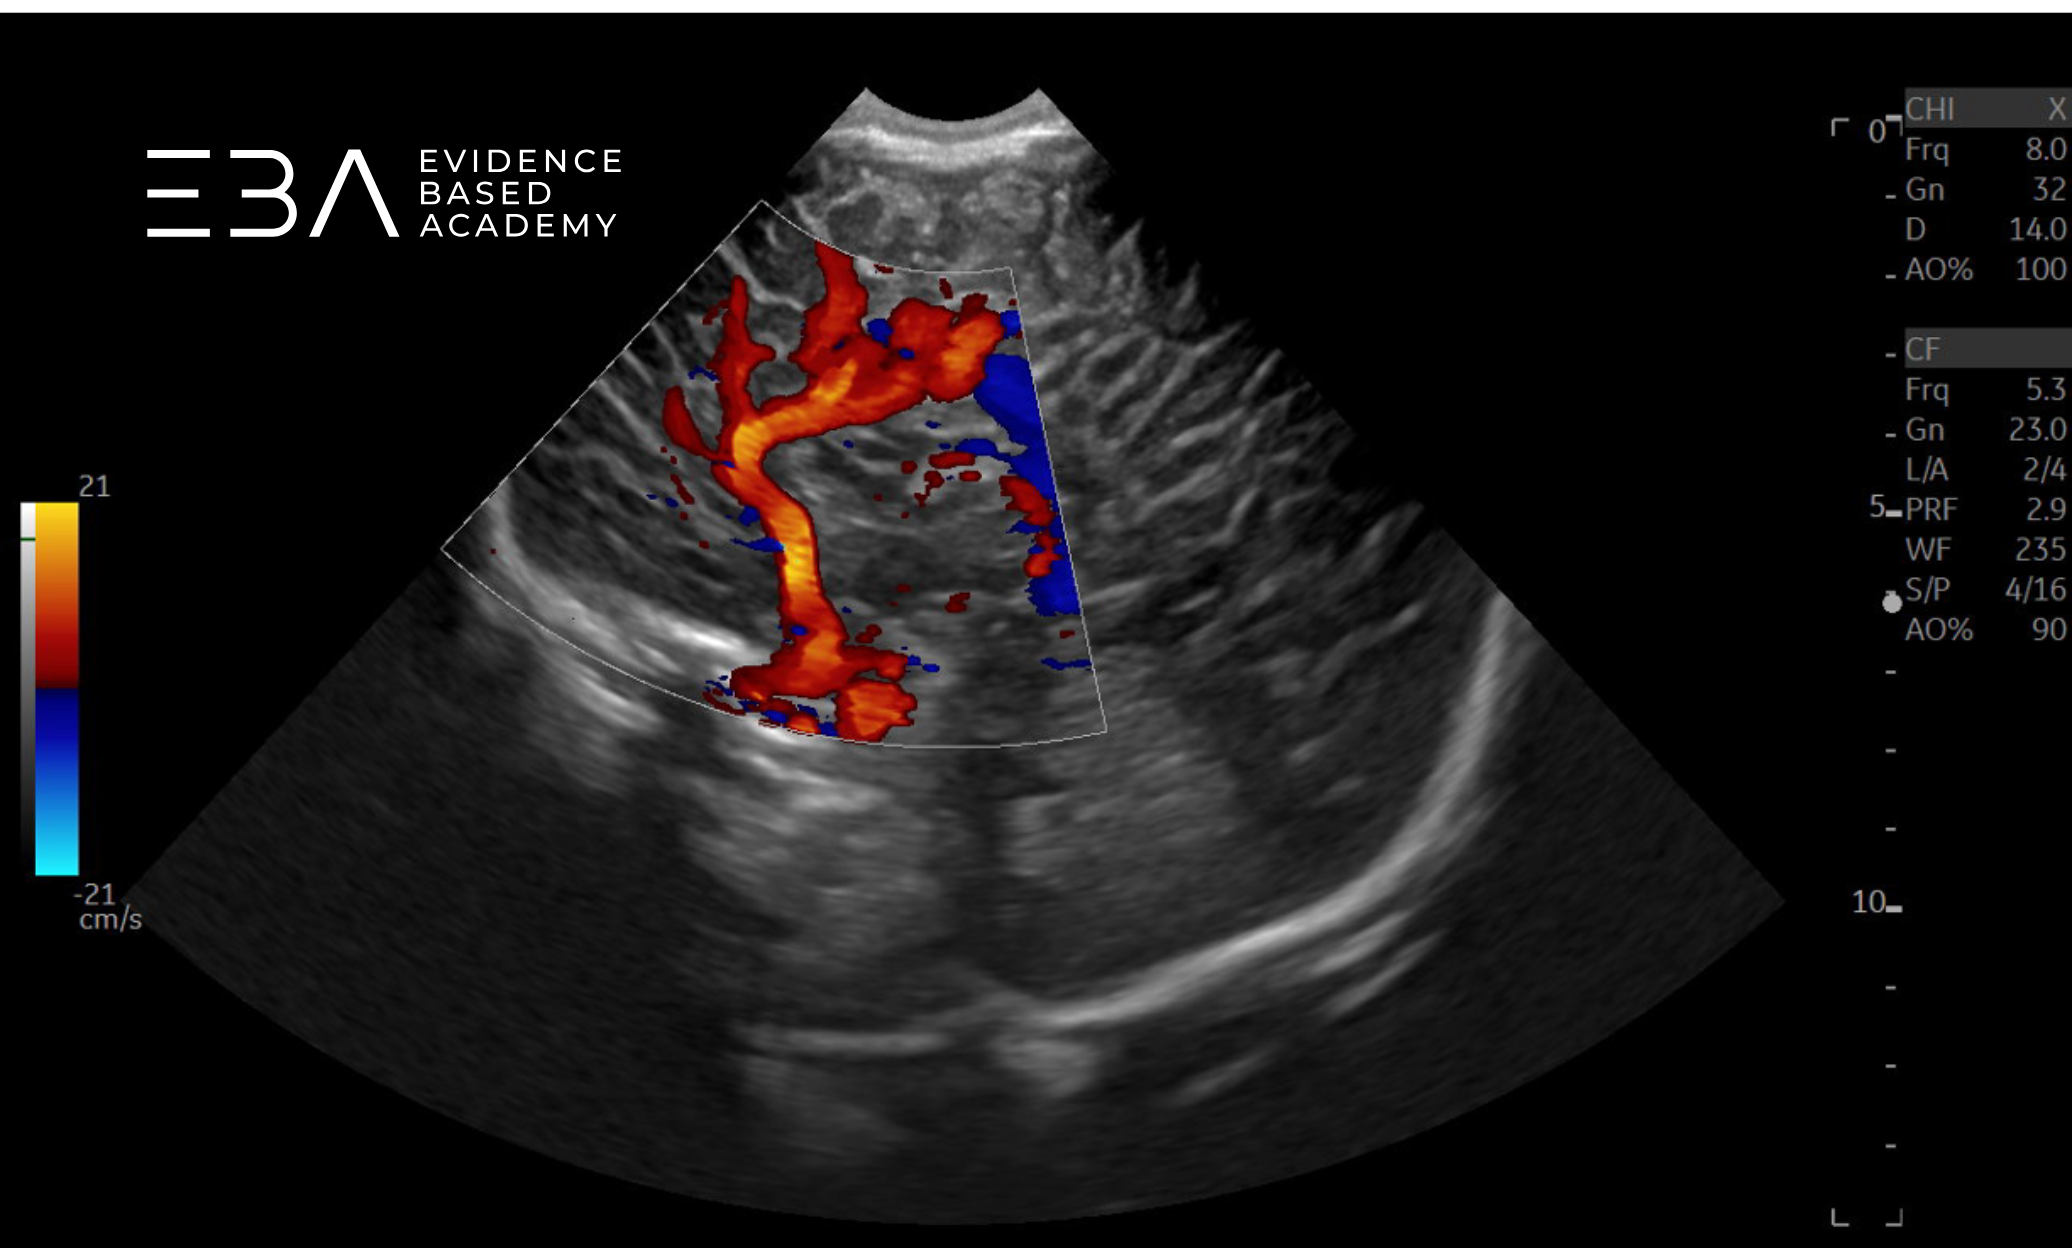

Badanie dopplerowskie

Badanie metodą Dopplera kolorowegopulsacyjnego umożliwia ocenę drożności naczyń wewnątrzczaszkowych oraz zmian hemodynamicznych mózgu noworodka (1, 2). Współczesne aparaty umożliwiają wizualizację przepływów rzędu 2 cm/s, co pozwala na uwidocznienie drobnych naczyń, takich jak naczynia pnia mózgu, żyły podwyściółkowe uchodzące do żył wzgórzowo-prążkowiowych oraz tętnice perforujące (3).

Obrazy koła Willisa w opcji Color Doppler uzyskujemy rutynowo w projekcji czołowej przez ciemiączko przednie lub w projekcji osiowej przez okno skroniowe. Wybór dostępu zależy od naczynia, które chcemy ocenić, lub od wygody badającego. Do rutynowego badania przesiewowego ciemiączko przednie jest zwykle wystarczające, natomiast do szczegółowej oceny koła Willisa lepszy jest dostęp przezskroniowy (6).